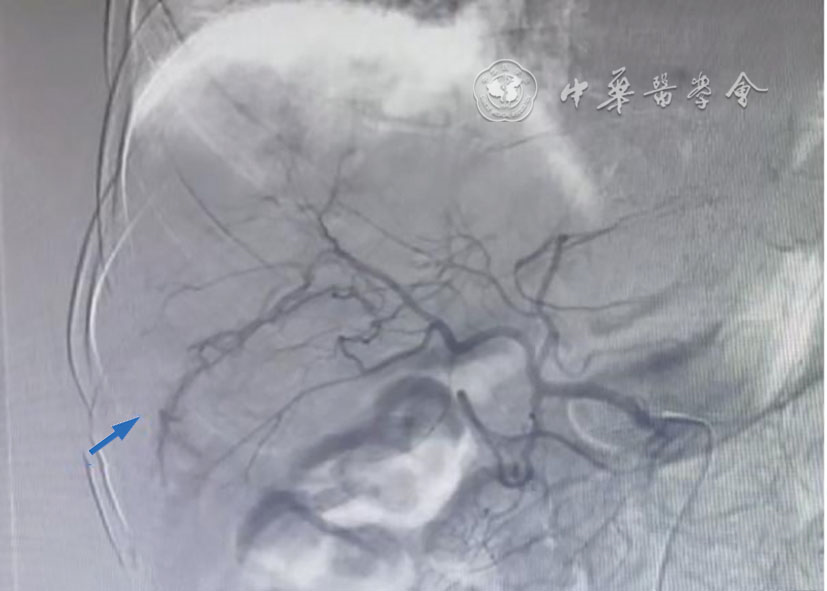

图5 经皮肝穿刺活检后肝脏数字减影血管造影图像。动脉早期可见造影剂自肝右前叶下段动脉分支溢出,呈一小段迂曲的管状(蓝色箭头),微导管超选择插管至肝右动脉分支,注射造影剂,可见胆管显影